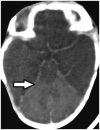

White Cerebellum Sign

On CT imaging, white (or dense) cerebellum sign is seen when the cerebellum appears dense with respect to the cerebral parenchyma. The “increase” in attenuation of cerebellum is in fact a relative hyperdensity caused by decreased attenutation of the brain (Fig. 30). It represents anoxic-ischemic cerebral injury, and has a very poor prognosis (32).

fig ft0fig mode=article f1

Fig. 30

caption a4

caption a8White cerebellum sign

Another sign associated with severe ischemic damage is the reversal sign, where the gray matter appears hypodense with respect to the white matter, in contrast to the normal appearance where gray matter is denser (57).